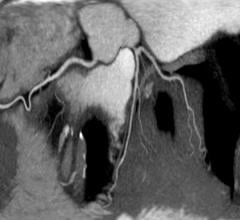

February 17, 2014 — At HIMSS 2014, Penrad released software that allows the creation of 3-D images of the carotid artery ...